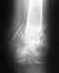

ЗДРАВСТВУЙТЕ! Женщина 62 года, упала, как результат, травма кисти. Кроме этого страдает артритом?/артрозом коленных суставов и возможно артритом?/артрозом? лучезапясных суставов. Помогите, пожалуйста, определить - есть ли переломы и в каких местах? Заранее благодарю.